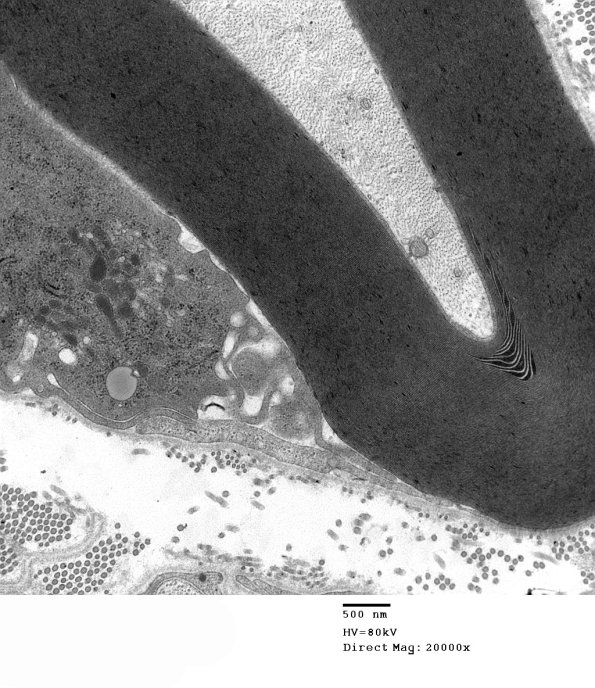

This series of images show a macrophage within the Schwann cell sheath with processes beginning the process of demyelination. (electron micrograph)